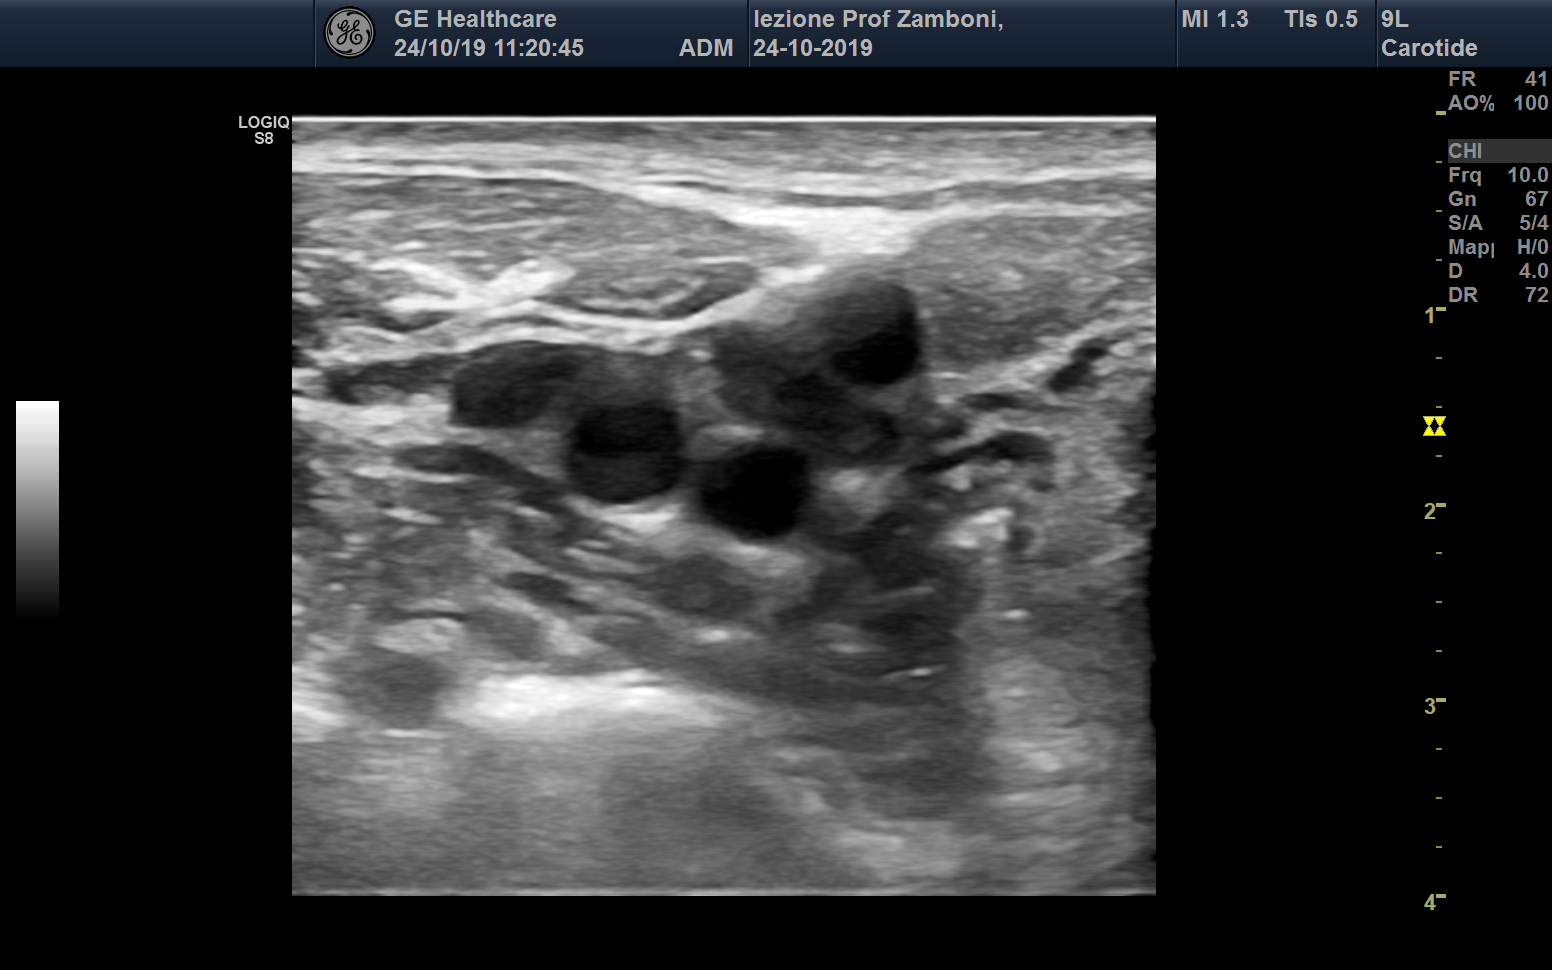

Biforcazione carotidea

JPEG image icon Biforcazione carotidea .jpg — JPEG image, 433 kB (444203 bytes)